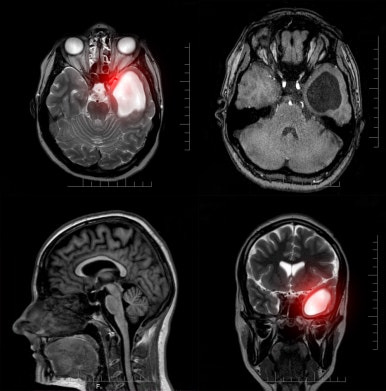

- MRI, CT 등 영상 검사로 정확한 위치 파악

- 신경학적 검사를 통한 기능 확인

- 조직검사를 통한 세포 성분 분석

- 종양의 종류(양성, 악성), 크기, 위치를 기준으로 치료 계획 수립